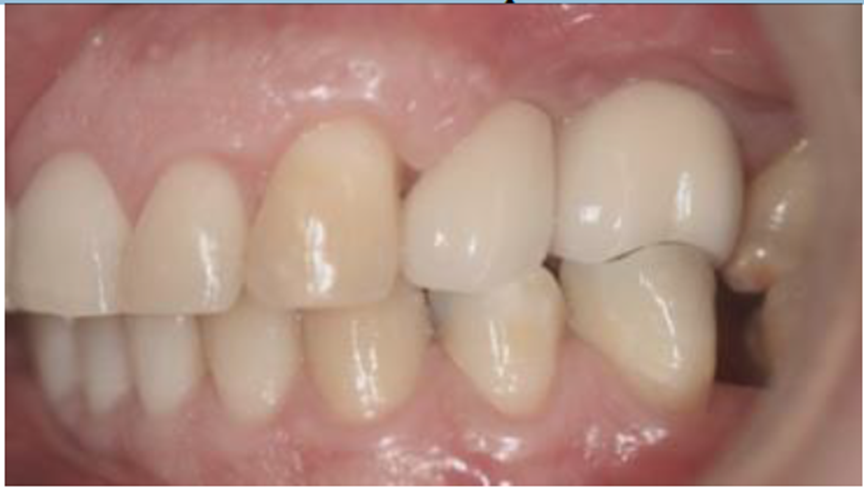

O paciente foi reabilitado com próteses parafusadas metalocerâmicas instaladas sobre pilares Ideale (Implacil De Bortoli – São Paulo – Brasil), conforme Figura 10.